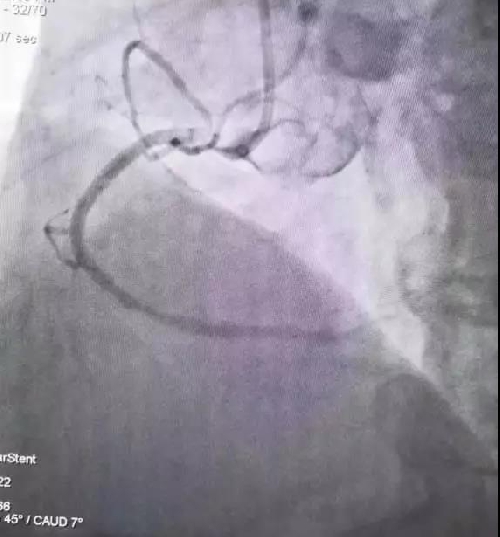

我院胸痛中心有很強(qiáng)的救治團(tuán)隊(duì),立即組織介入團(tuán)隊(duì)為患者進(jìn)行冠脈介入治療。手術(shù)開(kāi)始,造影后發(fā)現(xiàn)患者右冠脈近端幾乎完全堵塞,醫(yī)生使用球囊擴(kuò)張后,再通血流緩慢,再予冠脈內(nèi)給藥,支架支撐后,心肌功能逐漸改善,患者血壓也逐漸穩(wěn)定。手術(shù)過(guò)程中,患者一直保持清醒,能與醫(yī)生正常溝通交流。術(shù)后,患者恢復(fù)情況良好。